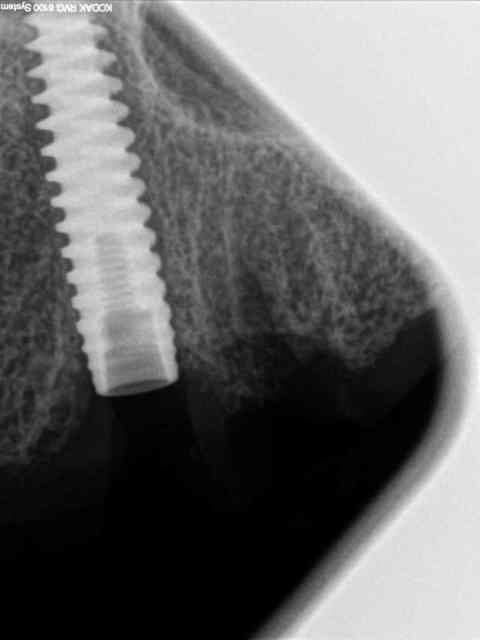

je vous mets les radios per-op.

secteur 1:

à l'aide du guide je détermine la position et l'axe de l'implant.

retrait du guide et contrôle radio puis pose des implants